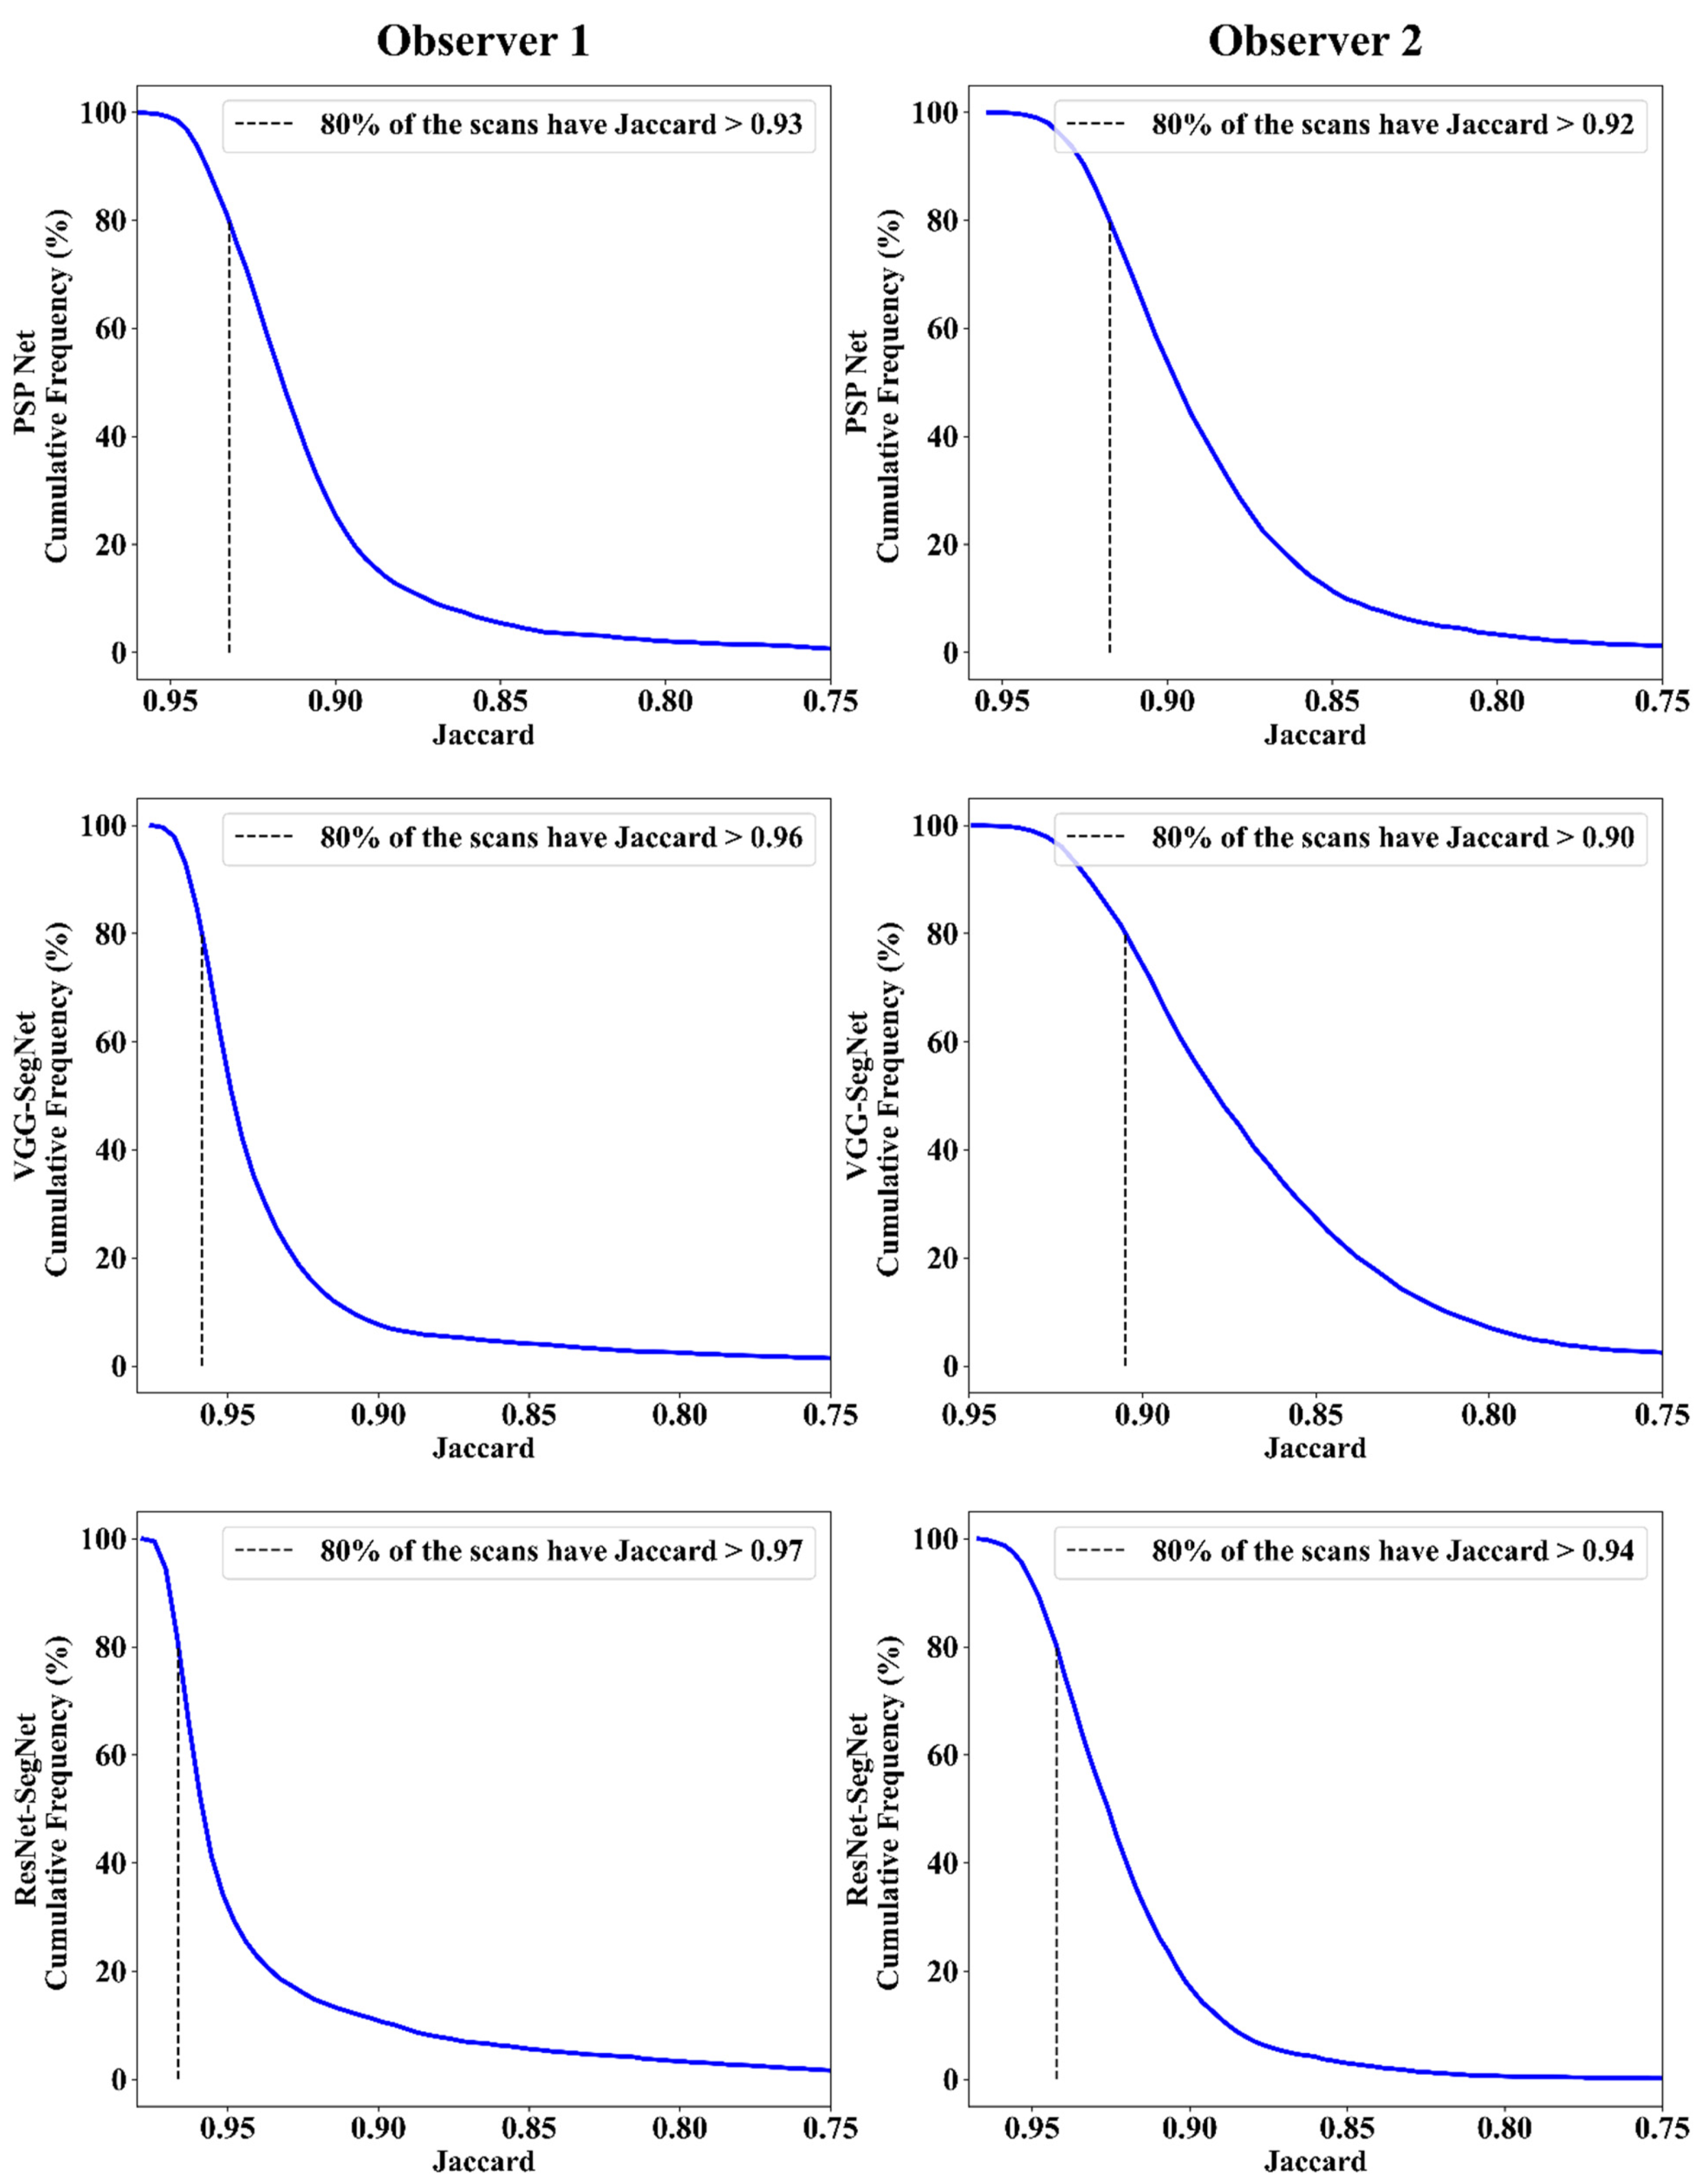

Jaccard Index and Dice Similarity

| Observer 1 | Observer 2 | Mean Obs. 1 & Obs. 2 | |||||||

|---|---|---|---|---|---|---|---|---|---|

| Attributes | PSP Net | VGG-SegNet | ResNet-SegNet | PSP Net | VGG-SegNet | ResNet-SegNet | PSP Net | VGG-SegNet | ResNet-SegNet |

| DS | 0.96 | 0.98 | 0.98 | 0.96 | 0.95 | 0.97 | 0.96 | 0.97 | 0.98 |

| JI | 0.93 | 0.96 | 0.97 | 0.92 | 0.9 | 0.94 | 0.93 | 0.93 | 0.96 |